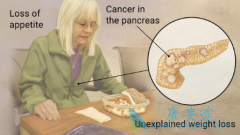

2018年2月,我国国家癌症中心发布了最新中国癌症统计数据。结果显示, 胰腺癌 位列中国城市男性恶性肿瘤发病率的第8位以及大城市(北京、上海)人群恶性肿瘤死亡率的第5位。 2014年我国胰腺癌新发约9.2万例,死亡约8.1万例。而2014年全年新发癌症患 ...

胰腺是身体内非常重要器官,如果患者和家属有心留意,肯定能发现不少胰腺疾病致死的报道。同时,胰腺的解剖位置隐蔽,早期癌症难以发现,导致很多患者确诊时就是局部晚期或转移性 胰腺癌 。 晚期癌症本身就很危险了,更何况是胰腺癌。其次是医疗因素 ...